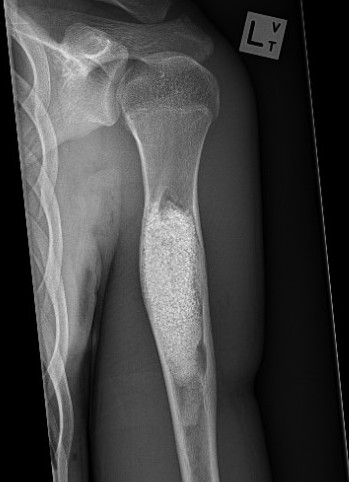

X-ray

Well-defined lucency

- thin sclerotic rim

- usually central

- thinned cortex with slight expansion

- thin internal septa

- can be multi-loculated

Fallen-Leaf (AKA fallen-fragment)

- with pathological fracture

- indicates that the lesion has no matrix and is fluid filled